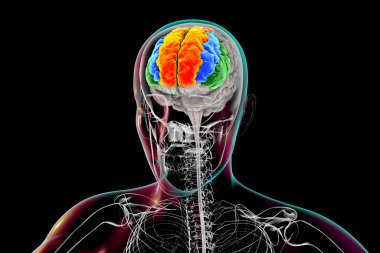

Tıbbi Konsept için sinir sistemi anatomisi olan 3D İnsan Beyni

MaviGrafikselresimlemeŞeffafİnsanSağlıkBaşıİlaçerkekkordonüç boyutlubiyolojikHücregövdeHastalıkİstihbaratİçeridebiyolojiBilimSistemAcıorgzihinomurgaelektronİşaretgörüntü oluşturmaanatomiomurilikbeyinMerkezGerginNörolojimikroskobikBeyin fırtınasıSıhhiyeanatomikSinirbeyincikcerebra3d oluşturmaüzerine siyahsinir hücresiBenzer İçerikler